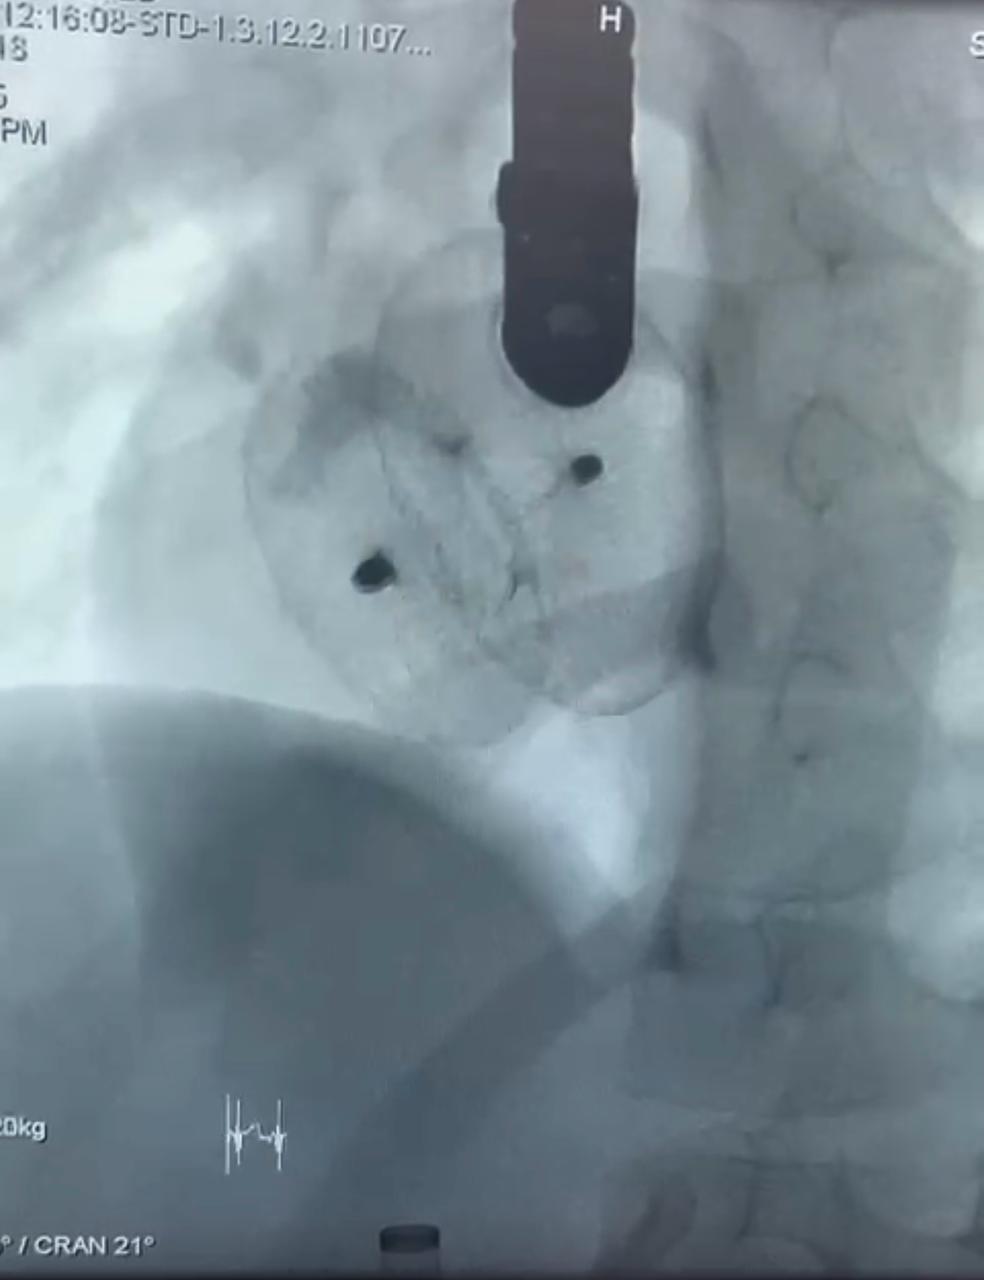

نجح الفريق الطبي بوحدة قسطرة الأطفال جامعة سوهاج، في إجراء ثلاث عمليات دقيقة ومعقدة بالقسطرة التداخلية لأطفال تتراوح أعمارهم بين ٣ و١٣ عامًا، في إنجاز طبي جديد يُضاف إلى سجل مستشفى سوهاج الجامعي، وذلك خلال يوم واحد فقط، باستخدام أحدث الأجهزة والتقنيات.

وقال الدكتور مجدي القاضي، عميد كلية الطب البشري ورئيس مجلس إدارة المستشفيات الجامعية جامعة سوهاج، بأن العمليات الثلاث تمثل نقلة نوعية في علاج العيوب الخلقية بالقلب لدى الأطفال، حيث تمت بإستخدام القسطرة التداخلية دون الحاجة إلى تدخل جراحي مفتوح، مما يُسهم في تقليل المضاعفات وتسريع معدلات الشفاء.

وأوضح الدكتور أحمد كمال عبدالحميد، المدير التنفيذي للمستشفيات الجامعية جامعة سوهاج، أنه تم علاج الطفلة حور (٣ سنوات) والتي كانت تعاني من ثقب بين الأذنين، وتم غلقه بإستخدام جهاز أمبلاتزر، والطفلة مريم علي (٦سنوات) التي كانت تعاني من ثقب بين الأذنين مصحوب بتضخم في القلب ونقص في النمو، وتم علاجها بإستخدام جهاز لايف تك، والطفلة فاطمة (١٣ سنة)، والتي كانت تعاني من ثقب بين البطينين، وتم إغلاقه بإستخدام جهاز كونار لايف تك، وهو من أحدث أجهزة إغلاق الثقوب عالميًا.